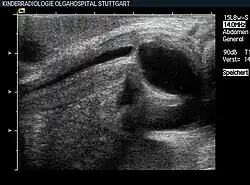

Zu den bildgebenden Verfahren gehören die (retrograde) Urethrographie, bei der die Harnröhre mit einem Röntgenkontrastmittel aufgefüllt wird, um Harnsteine, Fremdkörper, Verengungen, Fehlbildungen, Tumoren und andere Auffälligkeiten zu identifizieren, sowie das Miktionszystourethrogramm, bei der die Blase über einen Katheter mit Kontrastmittel befüllt wird. Bei der Ausscheidung des Kontrastmittels können dann wie bei der Urethrographie Aussackungen oder Abflusshindernisse der Harnröhre erkannt werden.[23] Für die Ultraschalluntersuchung muss die Harnröhre zunächst mit Wasser oder Gleitmittel gefüllt werden. Diese Methode wird zur Abklärung von Harnröhrenstrikturen genutzt.[24]